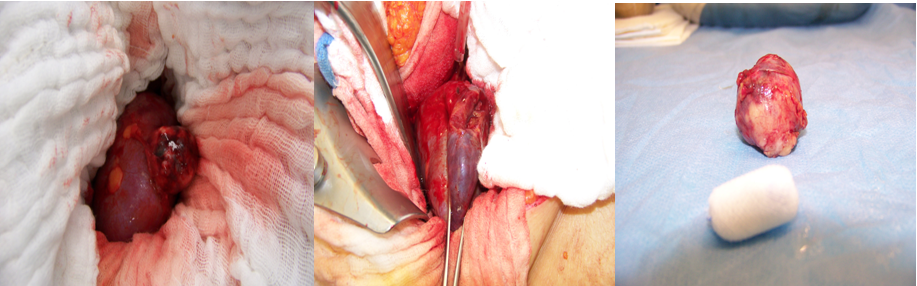

Wir entwickelten eine Technik der Ausklemmung der Niere während der Resektion, dabei wurde eine spezielle Klemme angewendet, um die Durchblutung des jeweiligen Abschnittes zu unterbinden (Partielle Ischämie). Durch diese Technik vermeiden wir eine komplette arterielle Ausschaltung der Niere und damit eine Verringerung der entstehenden Parenchymschäden (siehe Abbildung 1 [Abb. 1]).

Abbildung 1: Technik der offenen Nierenteilresektion mit partieller Ischämie

Bei der laparoskopischen Nierenteilresektion verwendeten wir eine Laparoskopieklemme wie bei der offenen Technik.